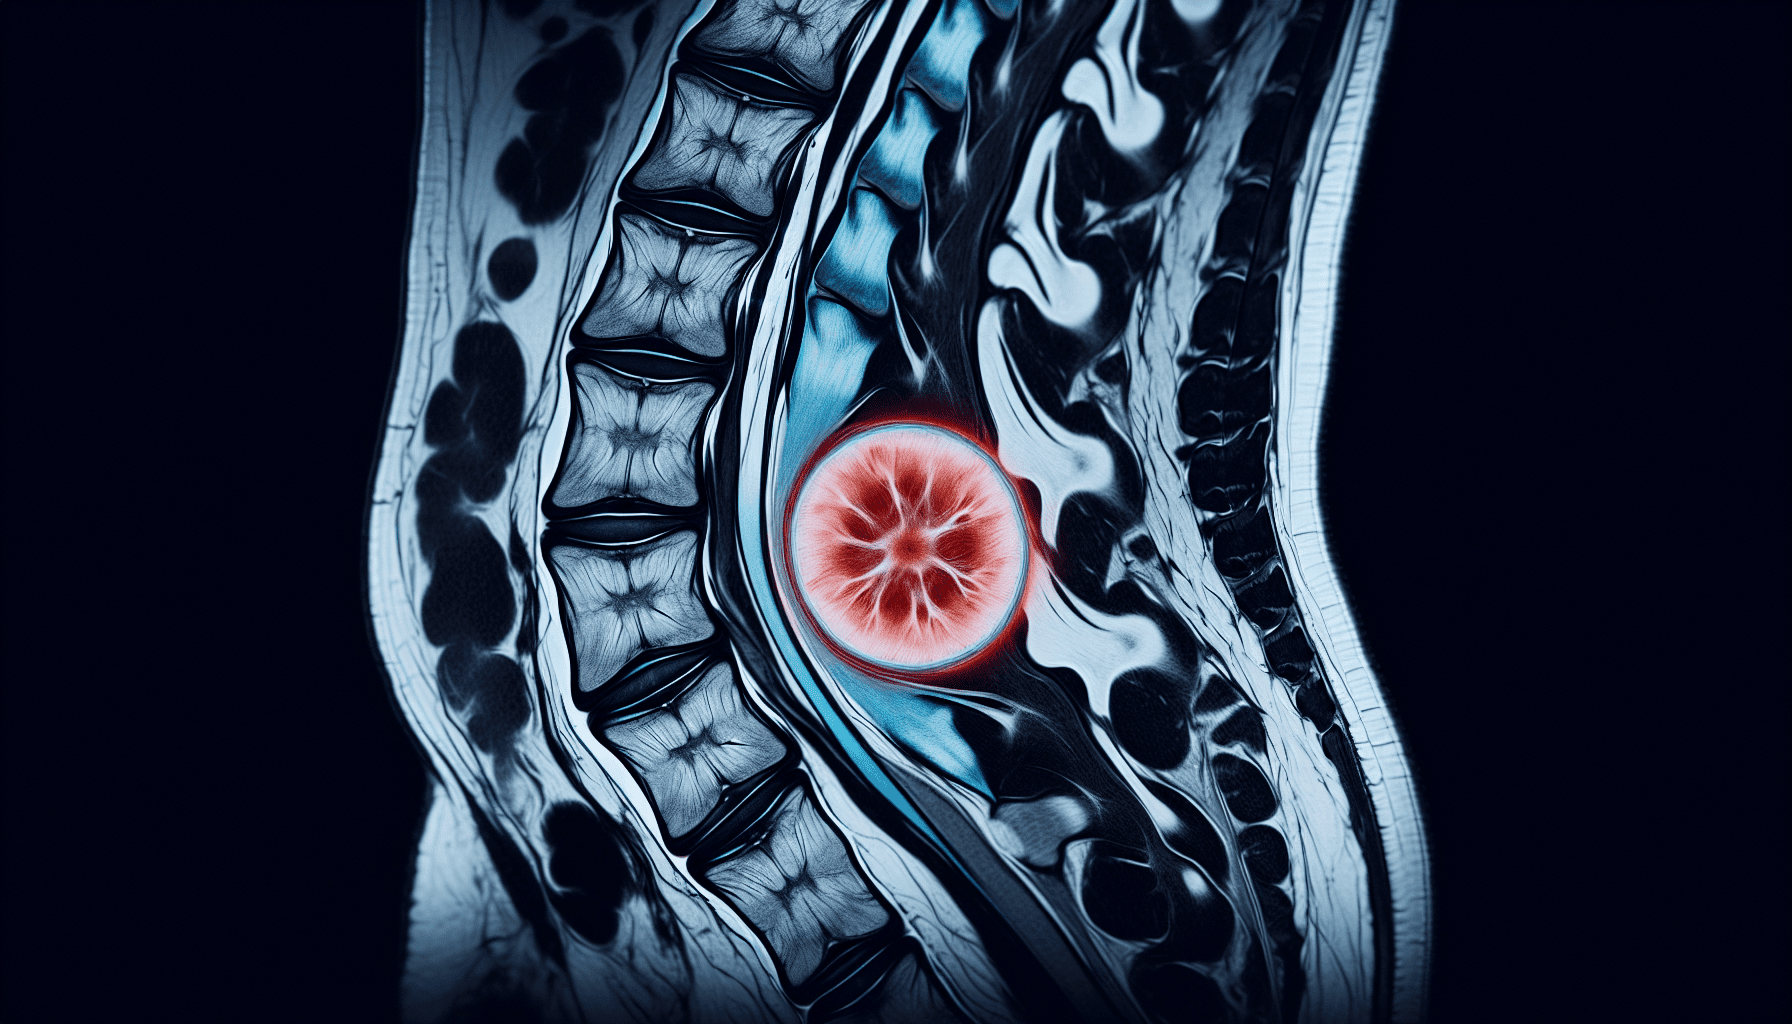

Imaging tests are crucial in diagnosing disc protrusion. Common imaging tests used to diagnose disc protrusion include:

- MRI (Magnetic Resonance Imaging): MRI uses powerful magnets and radio waves to create detailed images of the spine, showing the location and severity of disc protrusion.